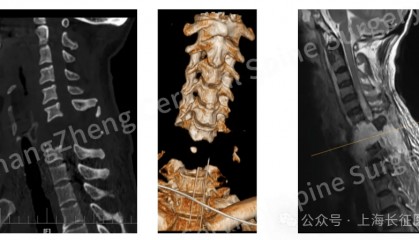

全球罕见!中国医生救回“身首离断”患者

从业近30年,上海长征医院颈椎外科病区主任陈华江教授接诊过无数凶险的颈椎外伤患者,但称得上是“身首离...